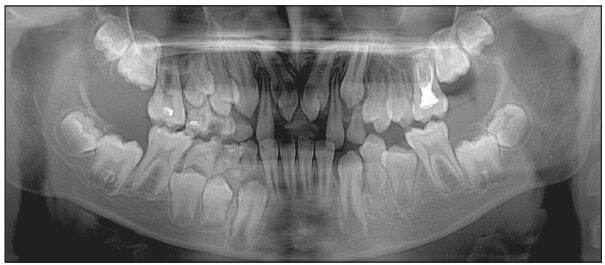

Дальнейшее ортодонтическое воздействие при помощи нижнечелюстной пластинки с расширяющим и удлиняющим зубной ряд винтами и искусственными зубами в боковых отделах было направлено на создание места в зубной дуге для прорезывания ретенированных премоляров нижней челюсти. Произведено удаление сверхкомплектных зубов в области 4.4 и 4.5 зубов. Через восемь месяцев отмечено прорезывание премоляров нижней челюсти справа (рис. 5).

Рис. 5. Ортопантомограмма Ф. А., 12 лет, на этапе лечения

В этой связи искусственные зубы были сошлифованы, съемный аппарат оставлен для сохранения протяженности нижней зубной дуги в области премоляров. Продолжительность комплексного лечения и наблюдения за формированием прикуса у пациента Ф. А. составила четыре года. Иллюстративный материал (рис. 6, 7 и табл. 3) наглядно демонстрирует успешность примененной тактики лечения.